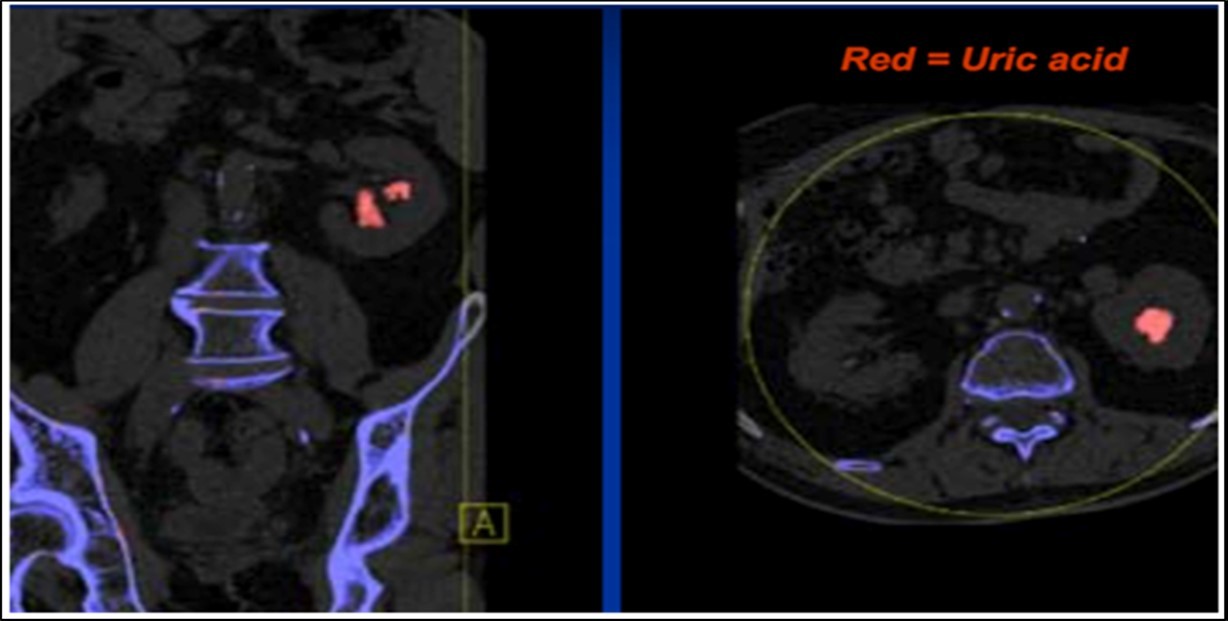

The attenuation difference is shown in colors. In graph 1, the 1.15 ratio represents threshold between uric acid and other stones. If a data point corresponding to a stone with unknown composition falls below this line, the algorithm will characterize such stone as a UA stone and will assign it a predefined red color. And if it falls above the line it will be identified as a non-UA stone and will be shown blue 2.

Stone analysis, together with serum and 24-hour urine metabolic evaluation, can identify the etiology in more than 95% of patients 1. Preoperative prediction of stone type (figure 1 and figure 2) is crucial for therapeutic decision making and follow-up 2, 3, 4, 5, 6. Some studies have reported predictive role of dual energy CT scan for determination of stone type 7, 8, 9.